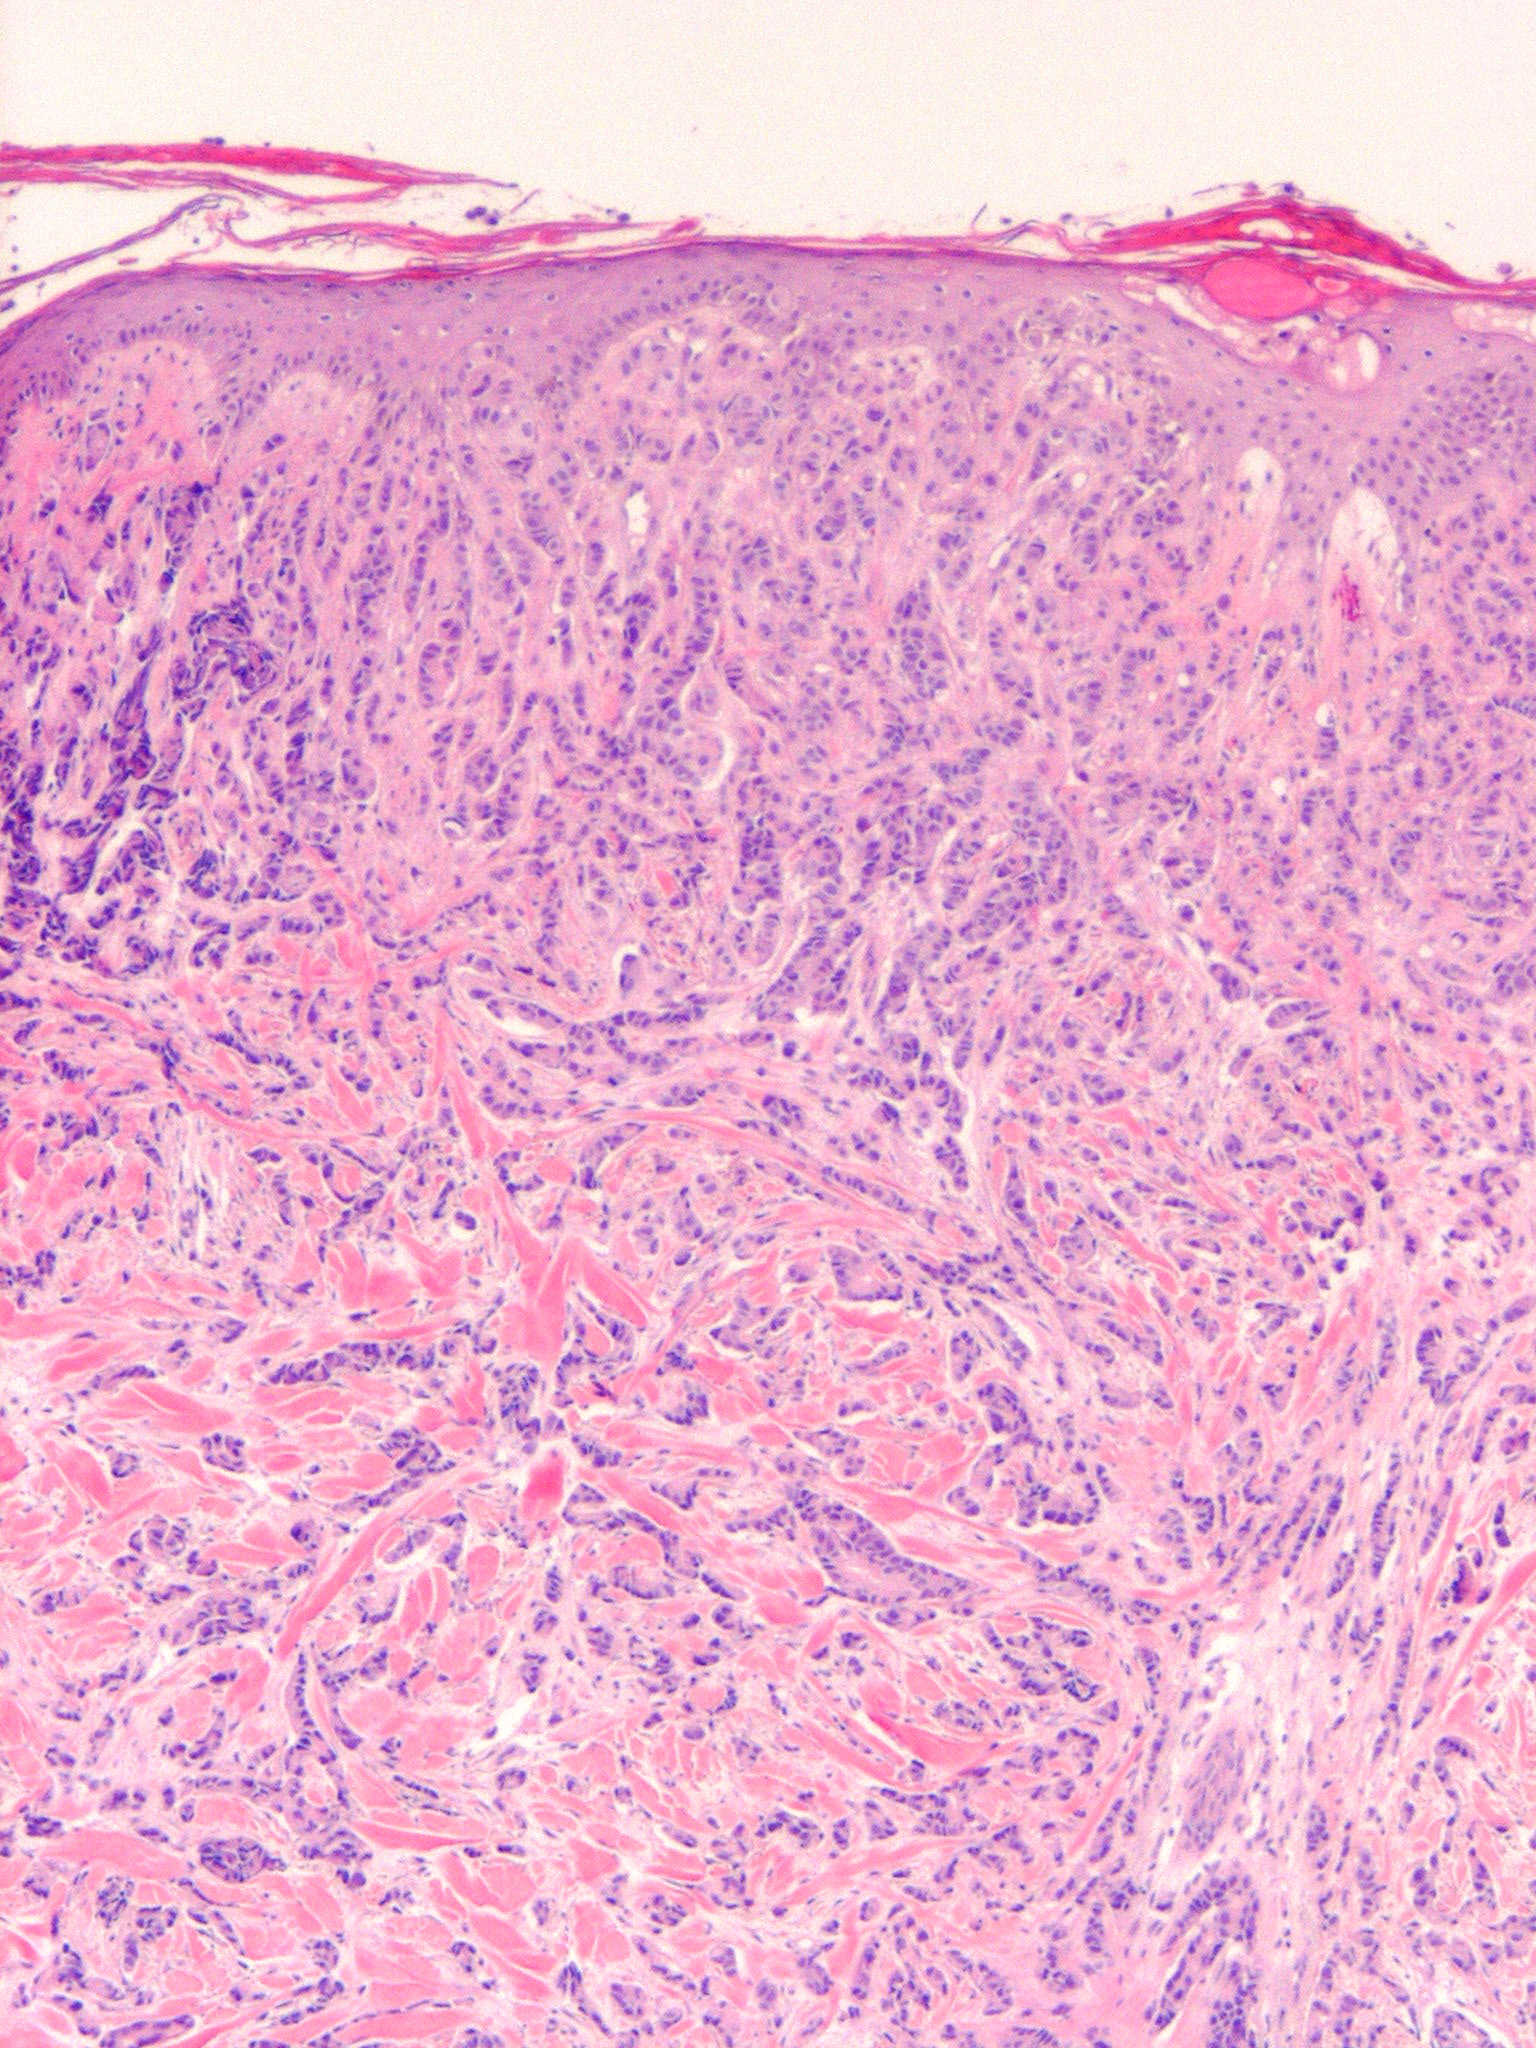

metastasis